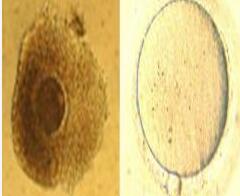

未成熟卵体外成熟技术(In Vitro Maturation,IVM)是试管婴儿领域的一项前沿技术,专门针对一些卵子成熟障碍的不孕患者,特别是那些顽固的多囊卵巢综合症、卵泡发育迟缓、卵巢过度刺激征的患者。

将未成熟的卵母细胞取出,在体外进行培养、受精,然后将胚胎移植到母亲子宫腔内生长。这种技术还可能避免药物和治疗的副作用,减少费用,降低促排卵的风险。

IVM作为最先进的辅助生殖技术之一,广州代妈公司生殖中心于2014年从美国加州大学引进该技术,为您顺利生育再增添保障。